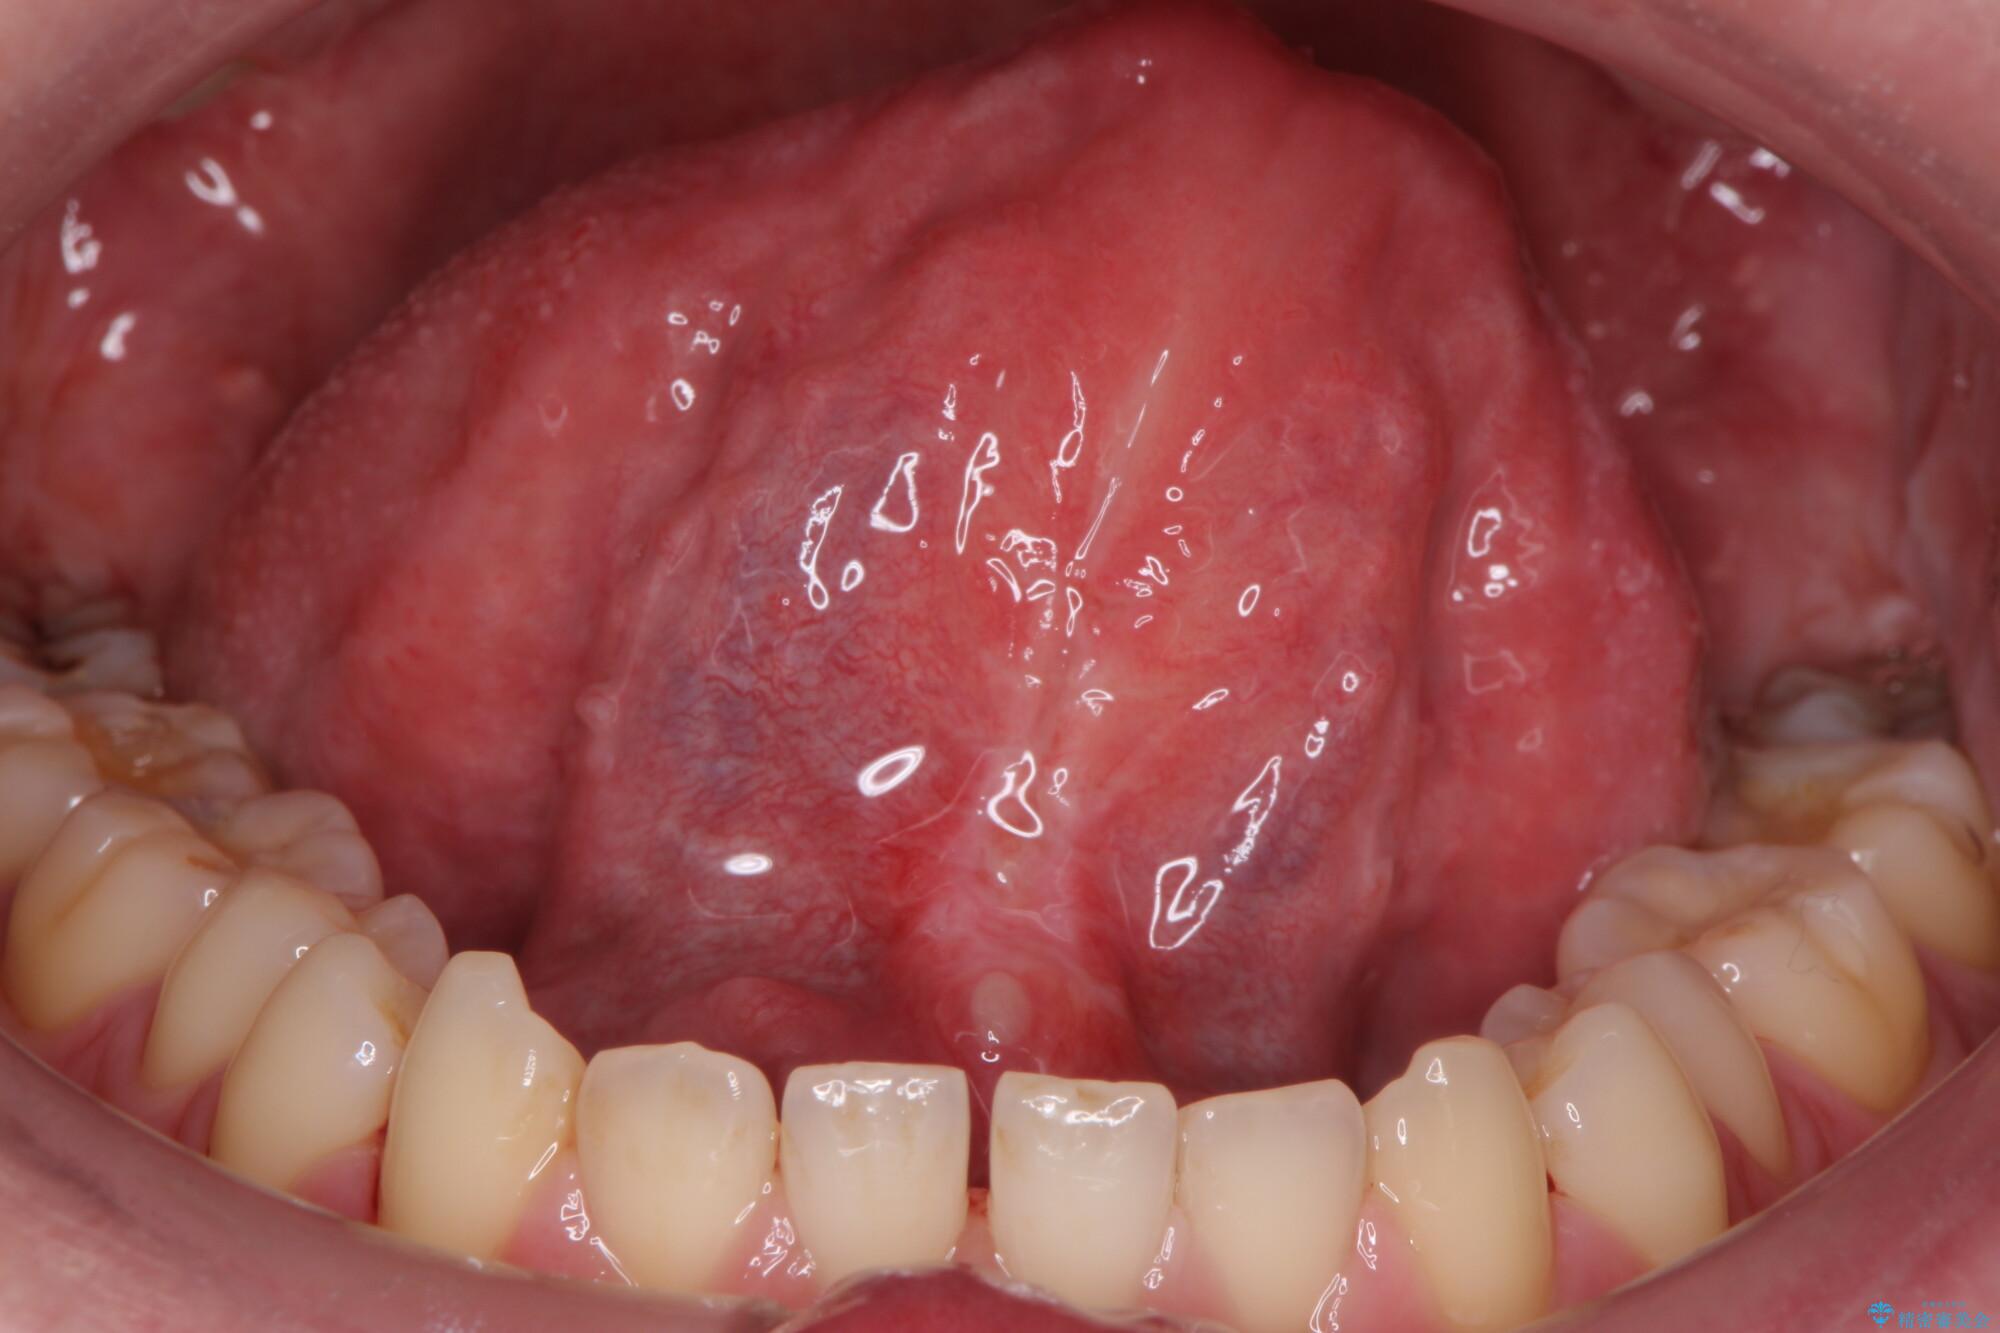

治療前

舌小帯を切除し滑舌を治したい 治療前画像 舌小帯を切除し滑舌を治したい 治療前画像